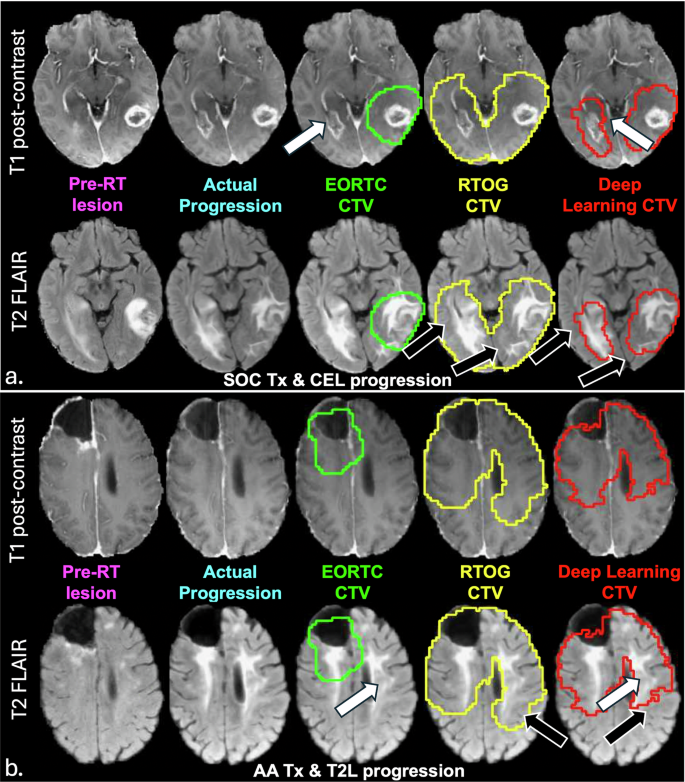

Visual comparison of deep learning and clinical CTVs for 5 example patients in the hold out test set are shown in Fig. 4 and Supplementary Fig. 5, with panels a and b of Fig. 4 corresponding to patients #16, and 2 in Supplementary Table 2, and panels A, B, and C of Supplementary Fig. 5 corresponding to patients #1, 15, and 13 in Supplementary Table 2. The patients in Fig. 4 were selected to highlight model performance in terms of both improved sensitivity or coverage of progression (white arrows) and specificity or sparing of normal brain tissue (black arrows), for representative patients exhibiting contrast-enhancing and non-enhancing lesion progression after SOC and bevacizumab + SOC, respectively. Visually, the predicted deep learning CTV (red contour) covered the entire tumor region on the progression scan in both examples, covering the region of new contrast enhancement that was missed by the EORTC CTV (green contour) in Fig. 4a, while simultaneously not overtreating beyond the progressed T2-lesion and sparing more normal brain tissue compared to the RTOG CTV (yellow contour). In the patient in Fig. 4b who experienced progression based on a growing T2 lesion, our deep learning CTV was again able to cover the large portion of the T2 lesion missed by the EORTC CTV, while sparing more normal brain than the RTOG CTV. The patient shown in Supplementary Fig. 5a who progressed by increases in both contrast-enhancing and non-enhancing lesions, demonstrated our multimodal MRI deep learning generated CTV’s (red contour) ability to outperform both the EORTC (green contour) and RTOG (yellow contour) defined CTVs, with the highest sensitivity, specificity, and PCC. Although the sensitivity of all models was >0.95 for the patient in Supplementary Fig. 5b who progressed via contrast-enhanced lesion, our model achieved 100% sensitivity with comparable specificity to the EORTC CTV (0.88 vs. 0.90), significantly reducing the extent of high-dose radiation to normal brain tissue (black arrows). Even in the patient example with worst model performance (Supplementary Fig. 5c) in terms of both sensitivity and PCC, our deep learning CTV still demonstrated improved specificity, while having the same sensitivity to the EORTC and RTOG CTVs that similarly missed covering a large portion of the progressed lesion.

a Example of contrast-enhancing lesion progression after a patient receiving standard-of-care (SOC) therapy (patient #16 of Supplementary Table 2). b Example of non-enhancing T2 lesion progression in a patient who received anti-angiogenic (AA) therapy in the form bevacizumab plus SOC (patient #2 of Supplementary Table 2). In both these patients, increased sensitivity to covering the progressed lesion (white arrows) was observed with our deep learning model (red contour) compared to the European Organization for Research and Treatment of Cancer (EORTC) defined clinical target volume (CTV) (green contour), while increased specificity was achieved compared to the Radiation Therapy Oncology Group (RTOG) defined CTV (yellow contour), demonstrating the ability of our approach to spare more unaffected brain (black arrows).